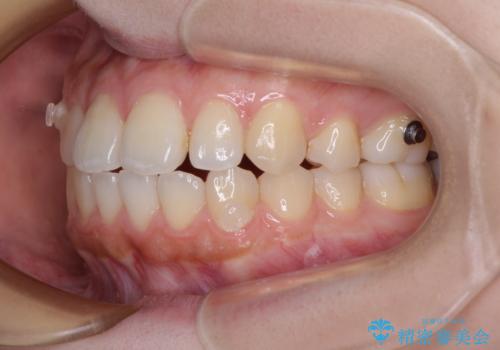

再矯正 開咬に後戻りした歯列をインビザラインで改善

- 矯正治療の後戻りを気にして来院された患者様です。

デコボコと上下前歯の隙間が気になるものの、しっかりと治療をしたいという意思はないとのことで、インビザラインの中でもアライナー数に制約のあるライトパッケージを用いて、治療できる範囲まで歯列を改善していくこととしました。

インビザラインは前歯部の開咬に効果的であることが多く、ライトパッケージにもかかわらず、十分満足のいく仕上がりとなりました。